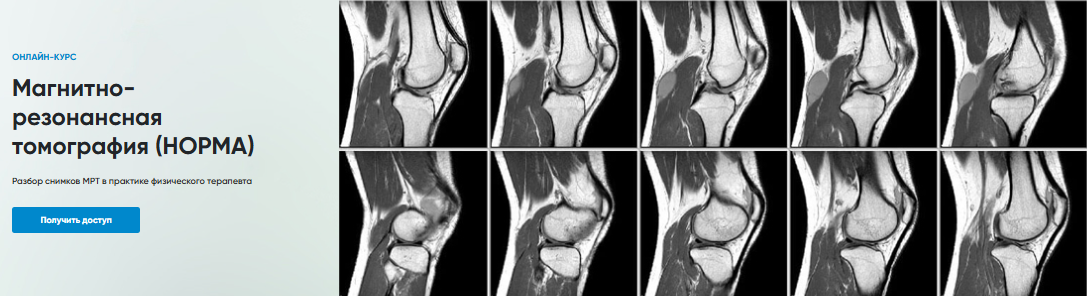

[Rehab Science] Магнитно-резонансная томография. Норма (Андрей Богатырев)

3 ноя 2024

Магнитно-резонансная томография (НОРМА)

Разбор снимков МРТ в практике физического терапевта

Программа

1. МРТ Коленного сустава

2. МРТ Голеностопного сустава

3. МРТ Запястье

4. МРТ Локтевого сустава

5. МРТ Плечевого сустава

6. МРТ Поясничного отдела позвоночника

7. МРТ Тазобедренного сустава

8. МРТ Шейного отдела позвоночника